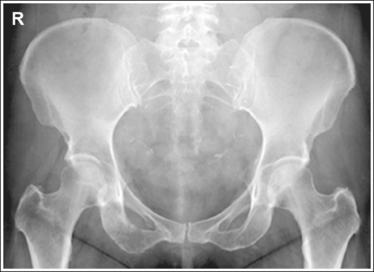

See Figures 7-21 and 7-22 and Box 7-5.

• Regarding the male and female pelves. Be aware of the bony architectural differences that exist between the male and female pelves (Table 7-2). These differences are the result of the need for the female pelvis to accommodate fetal growth during pregnancy and fetal passage during delivery.

The pelvis demonstrates an AP projection. The ischial spines are aligned with the pelvic brim, the sacrum and coccyx are aligned with the symphysis pubis, and the ilia and obturator foramina are open and uniform in size and shape.

• An AP projection of the pelvis is accomplished by placing the patient supine on the imaging table, with the legs extended and the arms drawn away from the pelvic area (Figure 7-23). To ensure that the pelvis is not rotated, judge the distance from the ASIS to the imaging table on each side. The distances should be equal.

• Pelvic rotation. A nonrotated AP pelvis projection demonstrates symmetrical ilia and obturator foramina. Rotation is initially detected by evaluating the relationships of the ischial spines with the pelvic brim and of the sacrum and coccyx with the symphysis pubis. The ischial spines should be aligned with the pelvic brim, and the sacrum and coccyx should be in alignment with the symphysis pubis on a nonrotated pelvis. If the pelvis is rotated into a LPO position, the left ilium is wider than the right, the left obturator foramen is narrower than the right, the left ischial spine is demonstrated without pelvic brim superimposition, and the sacrum and coccyx are not aligned with the symphysis pubis but are rotated toward the right hip (see Image 16).

The femoral necks are demonstrated without foreshortening and the greater trochanters are in profile laterally, whereas the lesser trochanters are superimposed by the femoral necks.

• Accurate leg positioning. To demonstrate the femoral necks without foreshortening and the greater trochanters in profile on an AP pelvis projection, the patient's leg should be internally rotated until the feet are angled 15 to 20 degrees from vertical and the femoral epicondyles are positioned parallel with the imaging table (Figure 7-24; see Figure 7-21). Sandbags or tape may be needed to help maintain this internal leg rotation. An AP pelvis projection may not demonstrate the proximal femurs with exactly the same degree of internal rotation. How each proximal femur appears will depend on the degree of internal rotation placed on that leg.